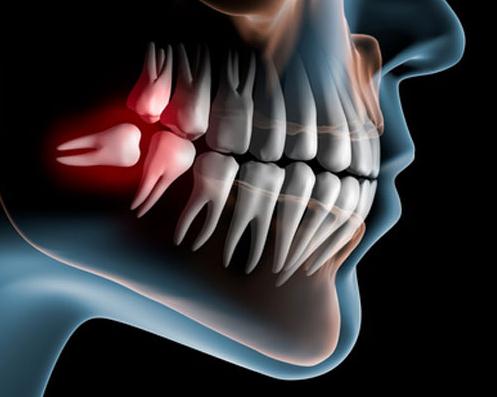

Der Mund- und Kieferraum des Menschen ist für die Weisheitszähne zu klein. Sie sind Opfer der Evolution geworden und brechen bei den meisten Europäern gar nicht erst durch. Viele Zahnärzte und Mund-, Kiefer-, Gesichtschirurgen entfernen Weisheitszähne vorsorglich. Ist dieses Vorgehen sinnvoll? Dass Weisheitszähne unweigerlich zu massiven Beschwerden führen, verweist Volker Kittlas, Arzt und Gesundheitsredakteur von Deutschlands größtem chirurgischen Gesundheitsportal ( www.chirurgie-portal.de (http://www.chirurgie-portal.de) ), ins Reich der Fabel.

Die Weisheitszahnentfernung zählt mit über eine Million chirurgischer Eingriffe zu den in Deutschland am häufigsten durchgeführten Eingriffen: in den meisten Fällen vorsorglich, um Komplikationen zu vermeiden. Die meisten Komplikationen – wie Infektionen oder vereinzelt auch Gesichtslähmungen – treten aber nach der Extraktion auf.

Bis ins hohe Alter kann ein Weisheitszahn, genau wie jeder andere Zahn, erkranken und Schwierigkeiten verursachen. Verkantet sich der Weisheitszahn so gegenüber dem Vorderzahn, dass Druck entsteht, die Zahnhygiene leidet oder Karies entsteht, wird jeder qualifizierte Zahnarzt zur Extraktion raten.